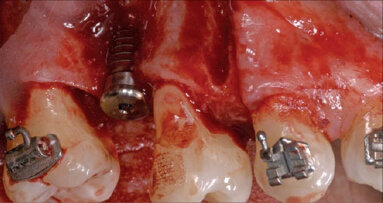

Obr. 1–5: Fotografi cká dokumentace počátečního stavu před parodontologickým ošetřením

Léčba byla zahájena instruktáží správné orální hygieny a motivací spolu s odstraněním zubního kamene a vyhlazením kořenů. Biologický faktor zubů 18, 17, 16, 26, 38 a 48 byl vyhodnocen jako klinicky beznadějný a zuby byly extrahovány. Po etiologické parodontologické léčbě byla provedena řízená regenerace tkání (Guided Tissue Regeneration = GTR) kolem zubů 15, 14, 12, 11, 21, 24 a 25. Osm měsíců po GTR byla realizována ortodontická léčba pomocí systému Invisalign (Align Technology).